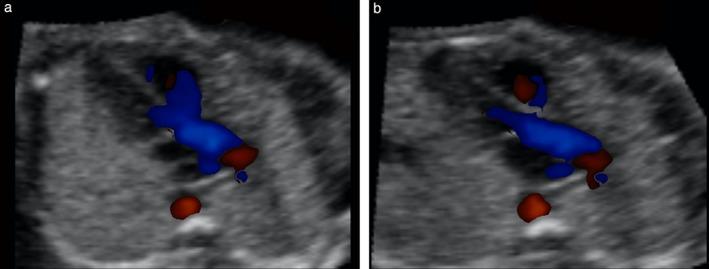

To evaluate the performance of color and bidirectional power Doppler ultrasound combined with Fetal Intelligent Navigation Echocardiography (FINE) in examining the fetal heart.

A prospective cohort study was conducted of fetuses in the second and third trimesters with a normal heart or with congenital heart disease (CHD). One or more spatiotemporal image correlation (STIC) volume datasets, combined with color or bidirectional power Doppler (S-flow) imaging, were acquired in the apical four-chamber view. Each successfully obtained STIC volume was evaluated by STICLoop™ to determine its appropriateness before applying the FINE method. Visualization rates for standard fetal echocardiography views using diagnostic planes and/or Virtual Intelligent Sonographer Assistance (VIS-Assistance®) were calculated for grayscale (removal of Doppler signal), color Doppler and S-flow Doppler. In four cases with CHD (one case each of tetralogy of Fallot, hypoplastic left heart and coarctation of the aorta, interrupted inferior vena cava with azygos vein continuation and asplenia, and coarctation of the aorta with tricuspid regurgitation and hydrops), the diagnostic potential of this new technology was presented.

RESULTS

A total of 169 STIC volume datasets of the normal fetal heart (color Doppler, n = 78; S-flow Doppler, n = 91) were obtained from 37 patients. Only a single STIC volume of color Doppler and/or a single volume of S-flow Doppler per patient were analyzed using FINE. Therefore, 60 STIC volumes (color Doppler, n = 27; S-flow Doppler, n = 33) comprised the final study group. Median gestational age at sonographic examination was 23 (interquartile range, 21-27.5) weeks. Color Doppler FINE generated nine fetal echocardiography views (grayscale) using (1) diagnostic planes in 73-100% of cases, (2) VIS-Assistance in 100% of cases, and (3) a combination of diagnostic planes and/or VIS-Assistance in 100% of cases. The rate of generating successfully eight fetal echocardiography views with appropriate color and S-flow Doppler information was 89-100% and 91-100% of cases, respectively, using a combination of diagnostic planes and/or VIS-Assistance. However, the success rate for the ninth echocardiography view (i.e. superior and inferior venae cavae) was 33% and 30% for color and S-flow Doppler, respectively. In all four cases of CHD, color Doppler FINE demonstrated evidence of abnormal fetal cardiac anatomy and/or hemodynamic flow.